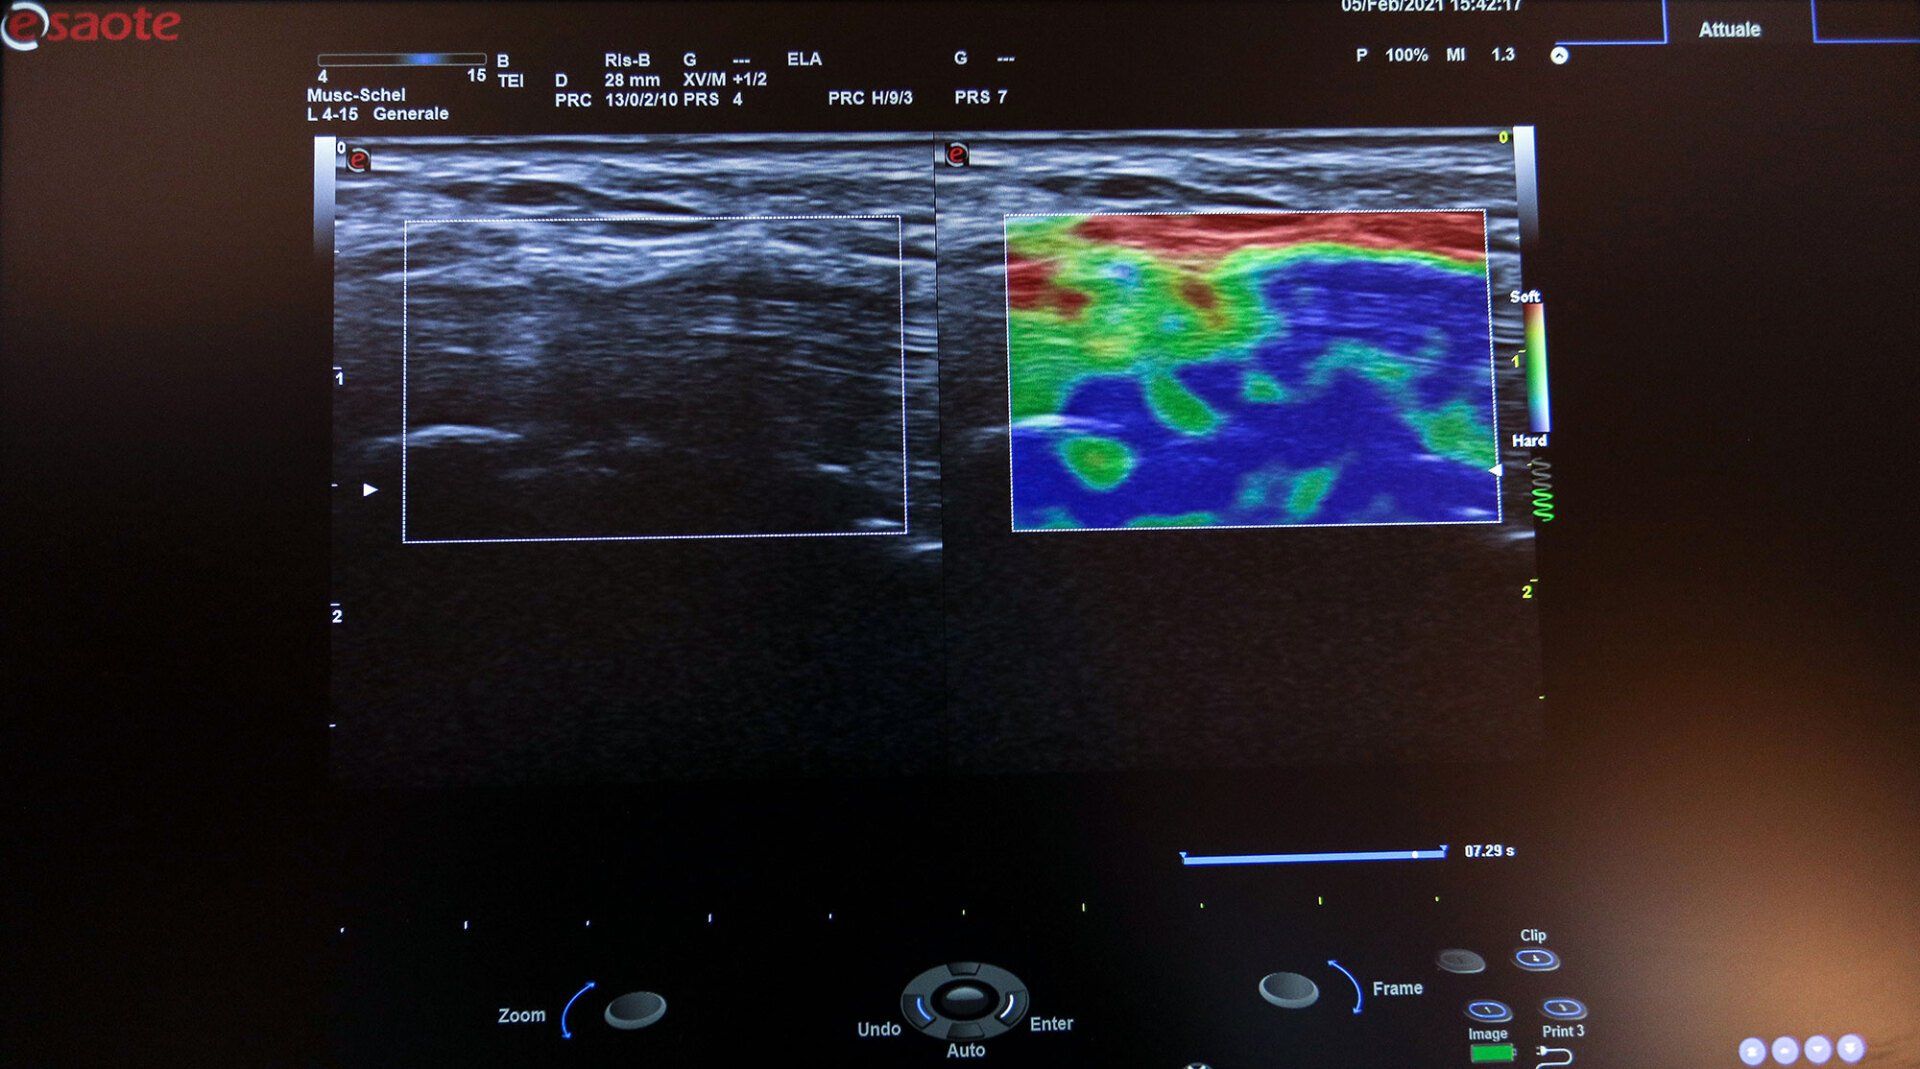

Ecografia HD a Terni: immagini ad alta risoluzione per diagnosi accurate

Per ottenere immagini dettagliate e nitide dei tessuti molli superficiali e degli organi interni, lo

Studio Braconi di

Terni

esegue esami ecografici utilizzando il sistema Esaote MyLab™ Eight.

Questa tecnologia si basa su metodiche diagnostiche non invasive che sfruttano ultrasuoni ad alta frequenza, permettendo di visualizzare le strutture interne con elevata definizione, senza l’impiego di radiazioni e senza effetti dannosi per l’organismo.

Utilizzando il modernissimo sistema a ultrasuoni Esaote MyLab™ Eight, il centro radiografico permette di ottenere immagini di eccezionale qualità per fornire una diagnosi sicura e affidabile dinanzi a ogni caso clinico. Tutte le ecografie eseguite all’interno dello studio permettono una visione chiarissima sui monitor LCD, nello specifico si effettuano le seguenti: